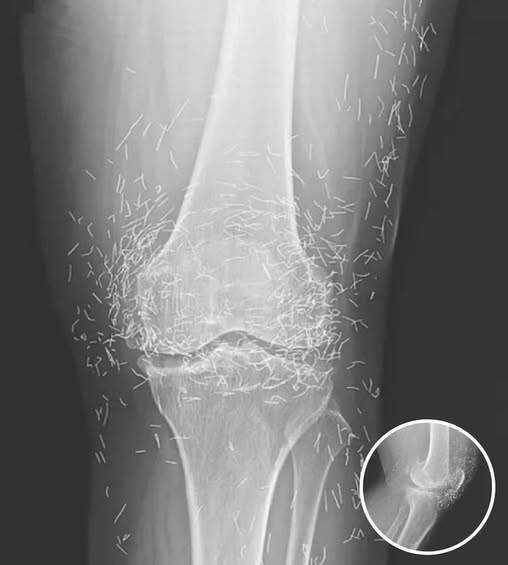

When a 65-year-old woman walked into a medical clinic in South Korea complaining of chronic, debilitating joint pain, the physicians expected to see the usual hallmarks of long-term degenerative disease. They anticipated narrowed joint spaces, telltale bone spurs, and cartilage erosion—the classic signatures of osteoarthritis. Yet, when the X-ray was developed, the team was confronted with a scene that defied conventional expectations. Staring back at them were hundreds of tiny, hair-thin gold needles, meticulously embedded deep in the tissue and muscle around her knees. This was no accident or sudden injury—it was the record of years of extreme measures taken to control pain, a physical manifestation of a decades-long struggle with osteoarthritis.

Desperate for a solution without chemical trade-offs, she turned to her culture’s deep-rooted traditions. In South Korea, acupuncture is a mainstream medical practice, widely trusted and accepted. However, the procedure she underwent went far beyond the typical insertion of needles. In a method known as gold thread or needle implantation, practitioners intentionally leave the needles inside the body. The theory is that gold provides ongoing stimulation to the acupuncture points, potentially offering a long-term reduction in pain signals. To the patient, it promised a life without pills; to the doctors examining the X-rays decades later, it raised alarms about long-term risks.

Metal fragments also complicate modern diagnostic procedures. In radiology, metal creates bright streaks, or artifacts, that obscure vital anatomy, making it difficult to monitor disease progression or detect issues like tumors or fractures. Metal needles pose an even greater hazard for MRI scans: strong magnetic forces could dislodge them, causing injury to nerves, tendons, or blood vessels. A procedure meant to relieve pain could inadvertently create life-threatening complications.

Published in the New England Journal of Medicine, her case has become a landmark warning. While she may have initially felt relief from the constant stimulation, she ultimately ended up with knees that were a literal minefield of metal. The X-rays act as a stark reminder that human bodies are not designed to house permanent foreign objects, no matter how precious the metal.